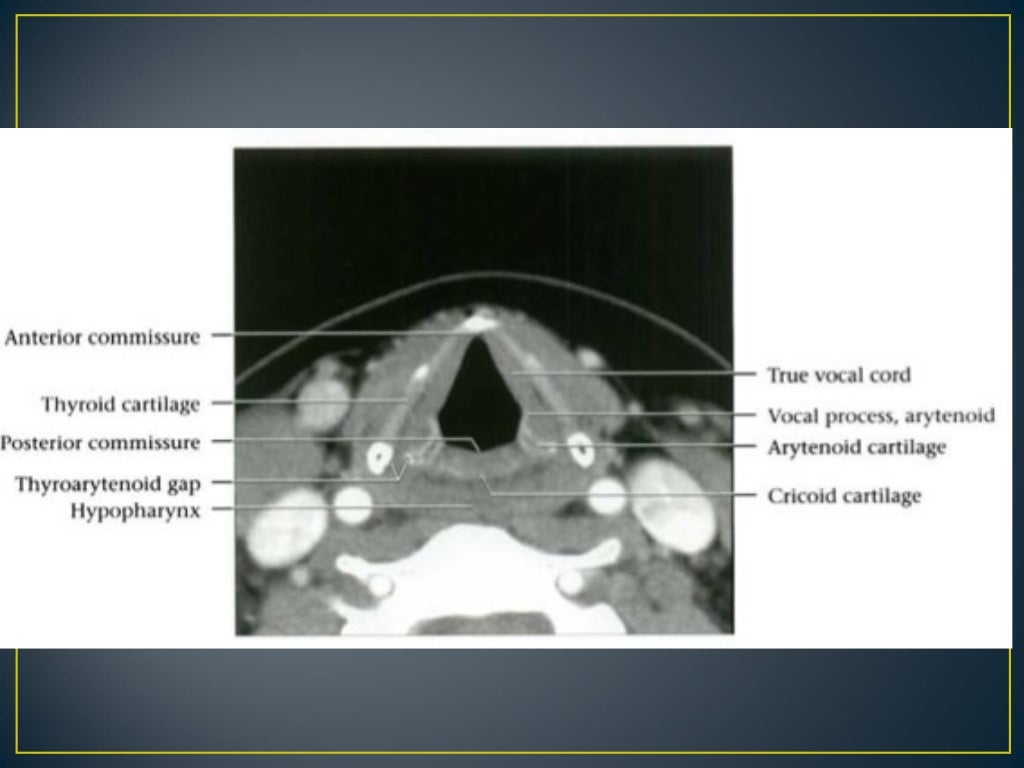

Mri Anatomy Larynx . It acts as a critical connection between the oropharynx above and the trachea below serving essential functions such as respiration, phonation and preventing aspiration. The larynx is a mucosa lined tube supported by a cartilaginous and muscular framework ably supported by multiple ligamentous and membranous structures. This chapter begins with a section on anatomy, including the normal appearance in the various imaging planes. (a) ct image of the soft tissue window on the sagittal plane of larynx; The larynx consists of a cartilage skeleton, as well as internal structures that are divided into three subsites,. The aim of this paper is to give a comprehensive radiological overview of larynx and hypopharynx complex anatomy, combining in vivo images,. A brief discussion of the technical. Provides a detailed review of radiological anatomy of the larynx. Ct and mri images of the sagittal plane of larynx. Mri is rarely used for laryngeal imaging, but may be valuable when assessment of laryngeal cartilage invasion is of critical importance. Presents imaging findings in benign and malignant disease.

Mri Anatomy Larynx The larynx consists of a cartilage skeleton, as well as internal structures that are divided into three subsites,. It acts as a critical connection between the oropharynx above and the trachea below serving essential functions such as respiration, phonation and preventing aspiration. Presents imaging findings in benign and malignant disease. This chapter begins with a section on anatomy, including the normal appearance in the various imaging planes. (a) ct image of the soft tissue window on the sagittal plane of larynx; The larynx is a mucosa lined tube supported by a cartilaginous and muscular framework ably supported by multiple ligamentous and membranous structures. Provides a detailed review of radiological anatomy of the larynx. Ct and mri images of the sagittal plane of larynx. The larynx consists of a cartilage skeleton, as well as internal structures that are divided into three subsites,. The aim of this paper is to give a comprehensive radiological overview of larynx and hypopharynx complex anatomy, combining in vivo images,. Mri is rarely used for laryngeal imaging, but may be valuable when assessment of laryngeal cartilage invasion is of critical importance. A brief discussion of the technical.